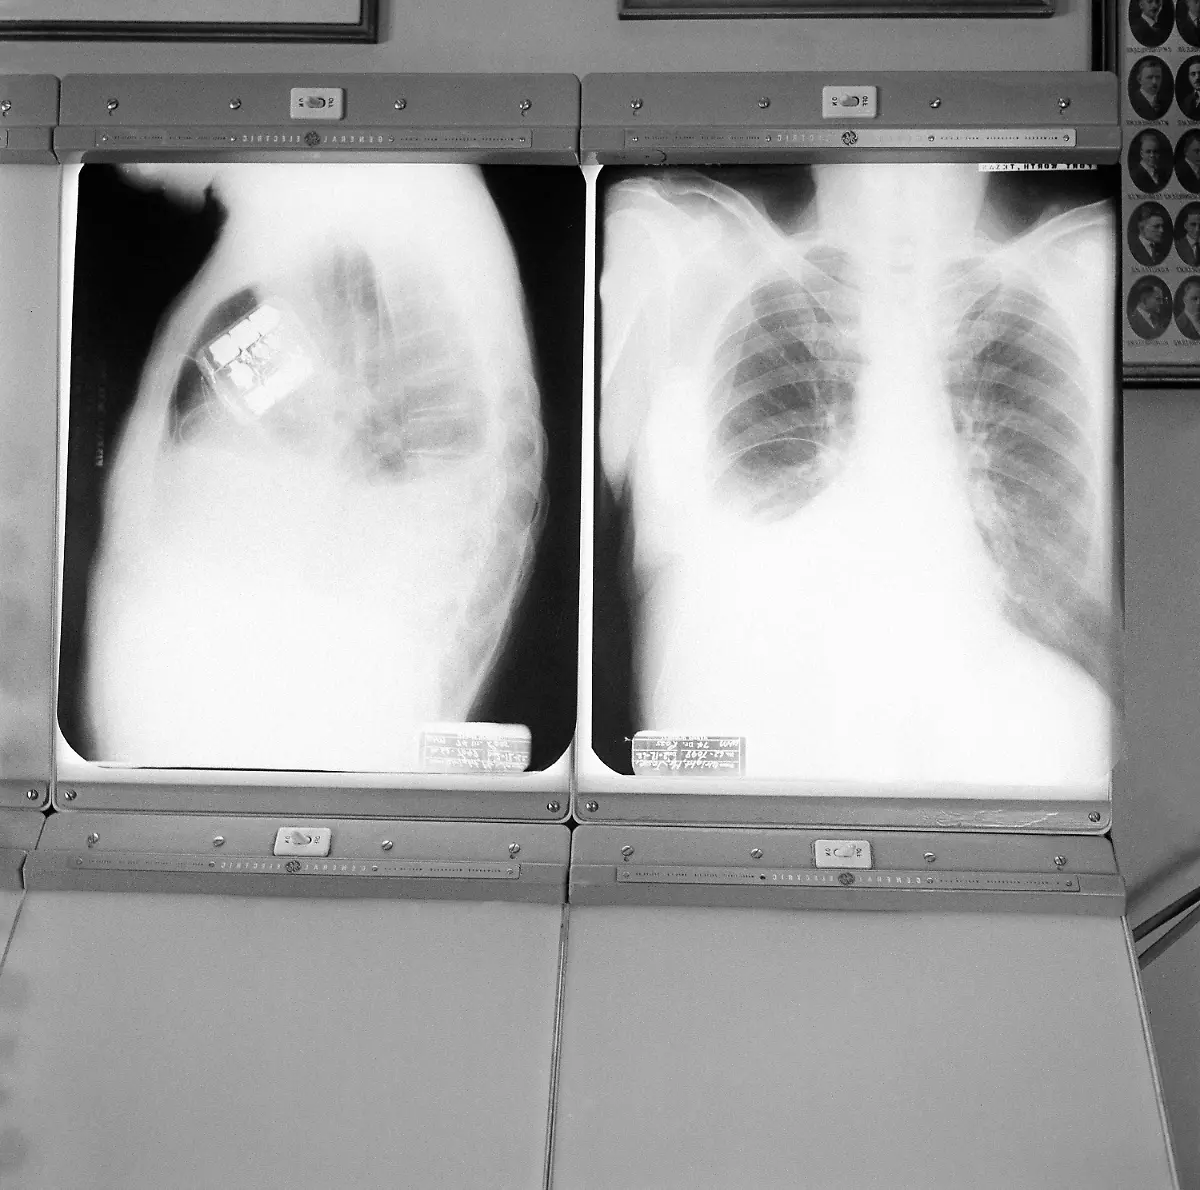

Geräte werden immer kleinerHerzschrittmacher retten Tausende Leben

Am 8. Oktober 1958 wird erstmals ein Herzschrittmacher in einen menschlichen Körper eingesetzt. Seitdem helfen die kleinen Kisten dabei, das Herz wieder im richtigen Takt schlagen zu lassen - und retten damit Leben.